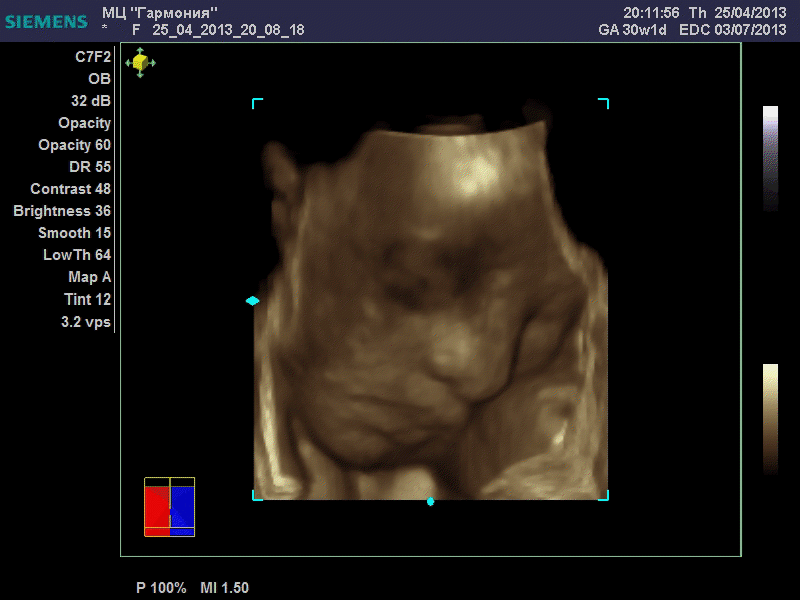

| Еще одна, качество ужасное..

| Вложения: |

|  image.jpg [ 60.32 КБ | Просмотров: 1190 ]